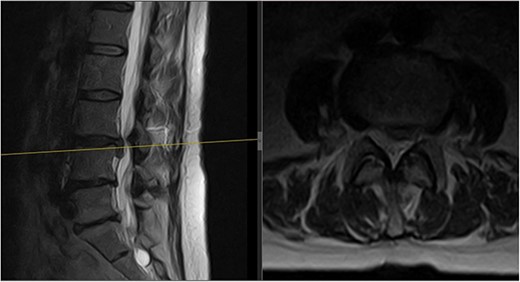

A 64-year-old female secretary presented with severe LBP and left anterior thigh pain that began 6 weeks prior to presentation whilst cleaning her house. She had no loss of bowel or bladder control, saddle anaesthesia, unintentional weight loss, or loss of appetite. A physical exam revealed decreased forward flexion, intact sensation, and intact motor function of the lower extremities. There was some tenderness in the left hip and gluteal regions. The straight leg raise was negative on the left but the femoral stretch test was mildly positive. Initial imaging showed an L3/L4 central and left paracentral disc extrusion with compression of the left L4 transiting nerve roots (Fig. 1). Benign haemangiomas were present at L2 and L4, along with a benign perineural cyst at S2. The patient was reassured and shown how to perform the motor control exercise programme as modified by the senior author (https://youtu.be/xJiAqVsfpRc) (Fig. 2).

Initial MRI scan of the lumbar spine: initial MRI scan of the lumbar spine performed in July 2022 showing the left-sided L3/4 disc prolapse.